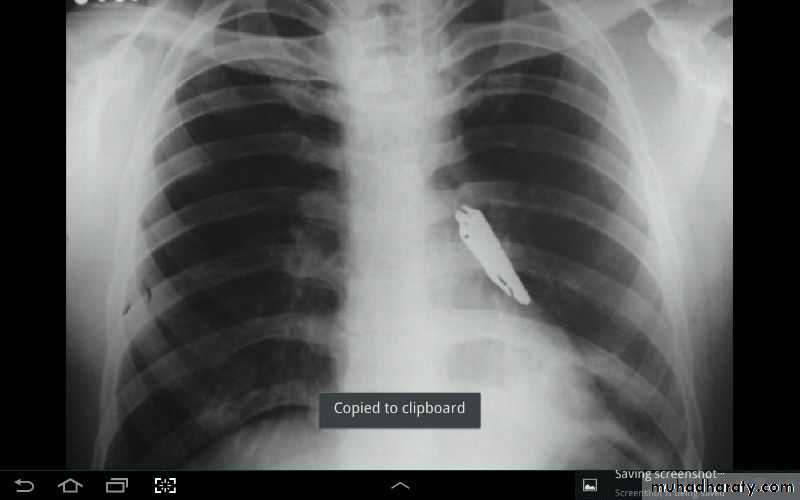

• Malposition